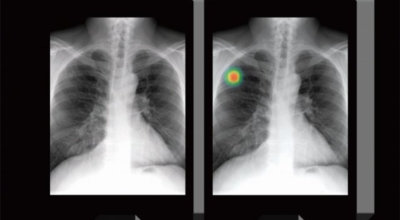

폐암 검사는 X-ray를 통해서 검사하는데 , 크기가 작거나 구석에 위치한 경우 확인이 어려운 경우도 있습니다. 그리고 조직 검사를 통해서 정확한 진단을 하게 되어요. 폐암이 발견되면 종양의 크기나 전이 여부 , 위치에 따라서 수술 여부를 결정하게 돼요.